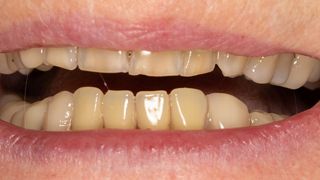

2b. Situation in the maxilla: the periodontal situation is stable.

2b